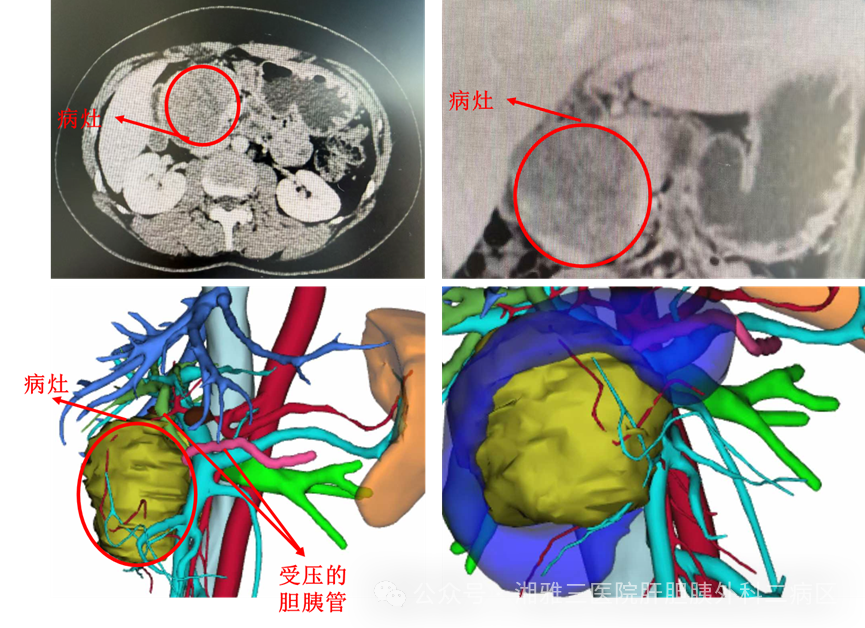

肝胆胰外科II科协助妇科海扶中心完成一例巨大胰腺癌的海扶治疗 撰稿:李巧燕 · 张良彬 2024年9月12日,中南大学湘雅三医院妇科海扶中心与肝胆胰外科II科、麻醉科成功合作,在优化静脉全麻地“保驾护航”下应用海扶(聚焦超声消融技术)成功治疗一巨大胰腺癌患者。医院麻醉科运用以长效+新型短······ 2024-09-13